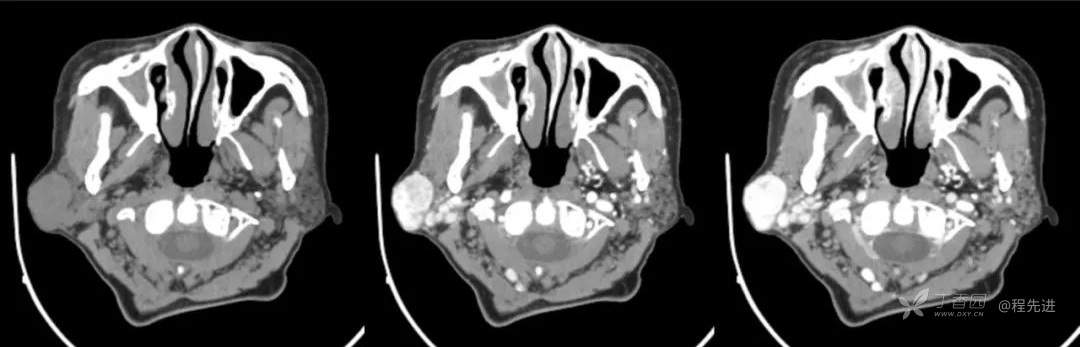

红五月特别精彩病例|发现右侧耳下肿物12年,罕见典型病例,见过就可以秒【病理公布】

简要病史:发现右侧耳下肿物12年,不痛,缓慢生长

既往史:19年前因右侧腮腺肿物在当地医院行手术(具体不详),17年前因右侧腮腺肿物复发再次在当地医院手术(具体不详)

体格检查:右侧耳下可扪及大小约3*3cm肿物,质地中,边界清,活动可,无明显压痛。颈部未扪及明显肿大淋巴结